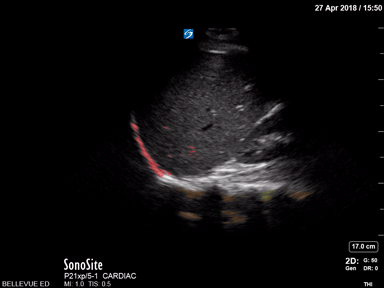

Pleural space Red: Diaphragm, Blue: Pleural space, Green: A lines, Orange: Spine Images: Dr. Lindsay Davis, Dr. Hannah Kopinski. Image Editing: Michael Amador and Dr. Matthew Riscinti